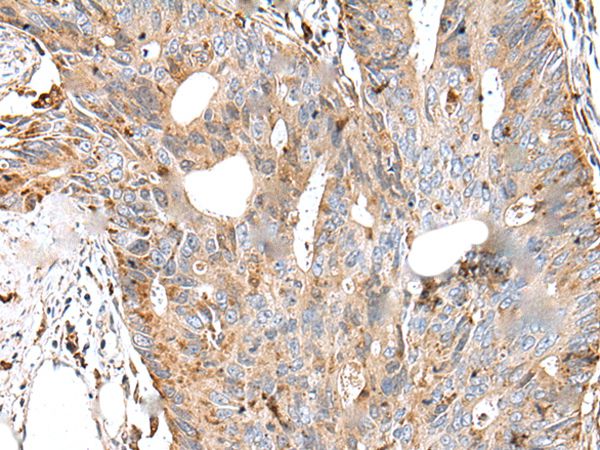

ApplicationsImmunoHistoChemistry

- Antibody SpecificityThe antibody detects endogenous levels of total CTSS protein.

- ApplicationsImmunoHistoChemistry

- Scientific DescriptionRabbit polyclonal antibody to CTSS